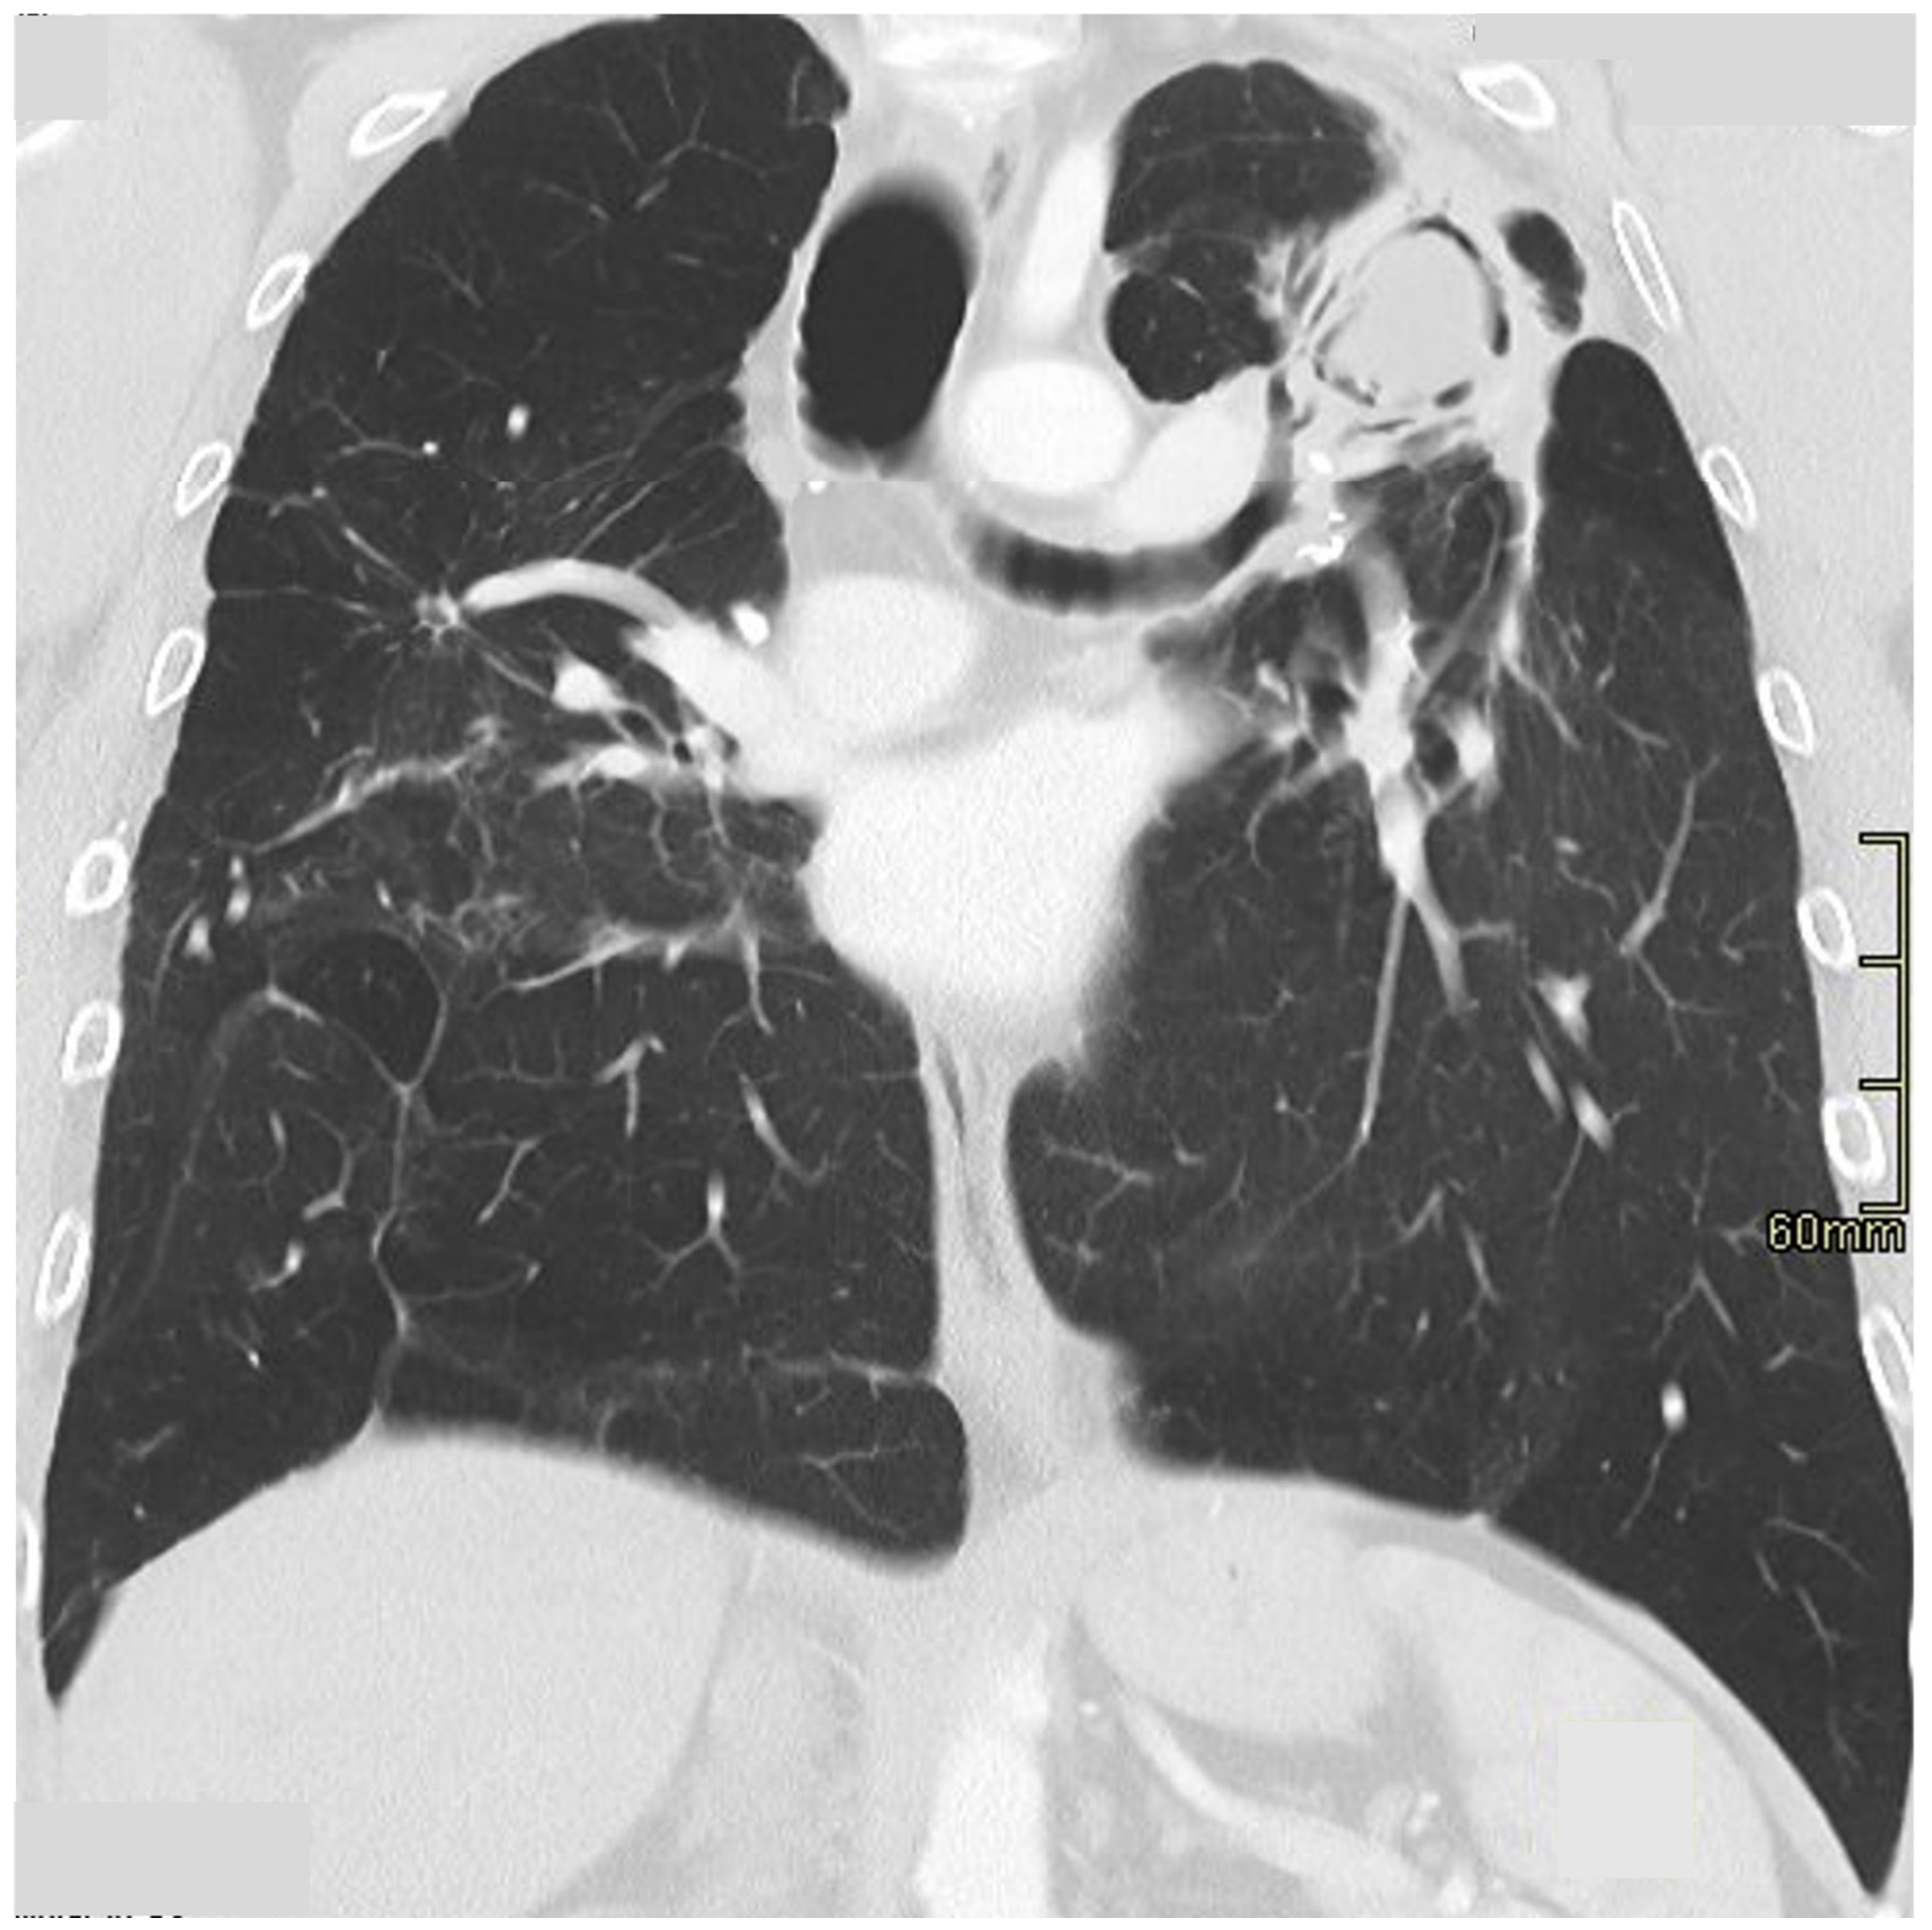

Clustering of micronodules around a larger central nodule gives rise to the so-called ‘galaxy sign’ [62], (Figure 3) reportedly seen in nearly one-third of patients [63], but not pathognomonic for sarcoidosis [64].

Figure 3.

Nodular sarcoidosis in a 46-year-old male patient. CT at the level of the aortic arch showing large nodules with surrounding micronodules (the ‘galaxy sign’) in both upper lobes (arrows).